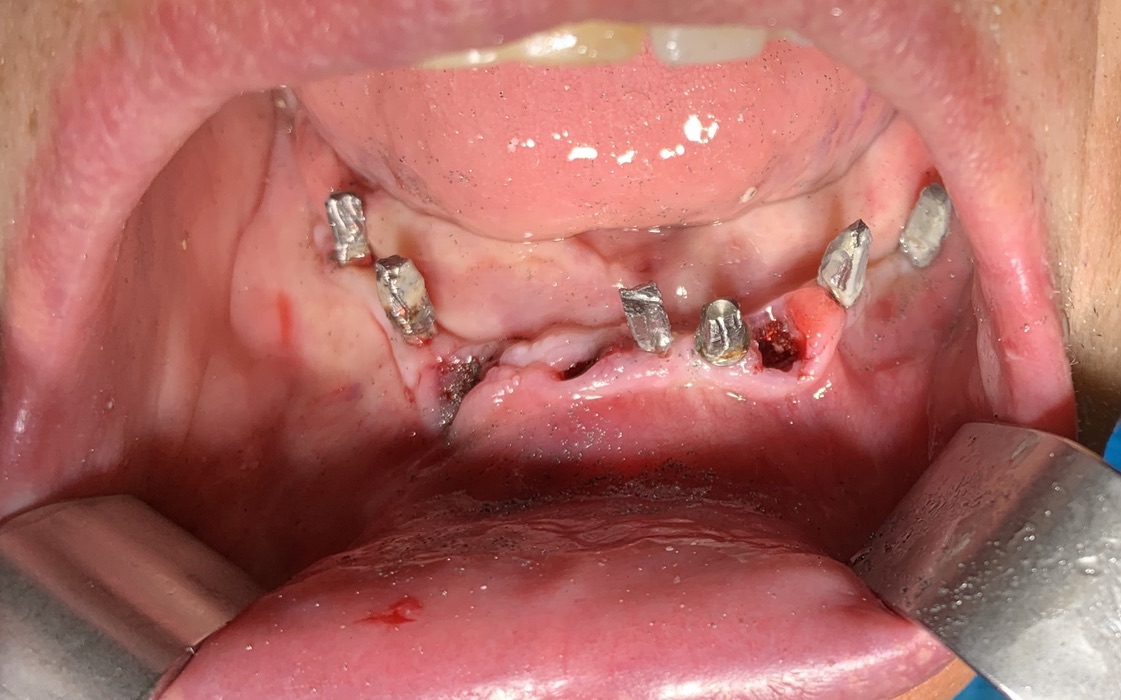

N° impianti esistenti     6 inferiori e 10 superiori

Data e n°interventi già fatti: prima del 2008 2 impianti. 10/2008: 1 impianto in 12. 07/2009: 2 impianti in 21 e 11. 11/2009: 4 impianti in 23,24,25,26. 05/2010: 1 impianto in 22. 07/2010: 2 impianti in 14,14. 08/2012: 2 impianti in 31,32. 05/2019: 2 impianti in 34,36.

Situazione estrattiva: impianti postestrattivi immediati

Come risulta dall’Estratto del Registro cronologico degli impianti su esposto il paziente si è sottoposto numerose volte ad interventi implantari,affrontando problemi settoriali mano a mano si presentavano. Tutti gli impianti sono convissuti sempre con elementi naturali che presentavano quadri variabili di parodontopatia. Mi sembra notevole questa situazione che viene da me riscontrata in moltissimi altri pazienti con casi di impianti che convivono con elementi naturali parodontopatici senza risentire delle infezioni, se la confrontiamo con le statistiche riportate dalla implantologia ‘osteointegrata’ ufficiale. Attribuisco questa felice condizione alla particolare forma nella zona di emergenza degli impianti di Tramonte. Essi sono dotati di collo lungo e sottile. Ciò garantisce la presenza di un manicotto di gengiva aderente molto stretto, inibendo di fatto la penetrazione dei batteri. Inoltre, non essendo costruito in più parti, (perchè è un monoblocco) non presenta cavità interne che quando sono colonizzate dai batteri costituiscono dei serbatoi molto efficaci nel perpetuare una condizione infettiva ed infiammatoria. Questa volta il paziente ha voluto affrontare l’intervento in anestesia generale, effettuato presso il nostro ambulatorio in Acquafredda con anestesista di lunga esperienza attrezzato. Il secondo aspetto strettamente dipendente dalla storia implantare del paziente è stata la presenza di disparallelismi corretti a fine intervento prima di protesizzarlo con circolare provvisorio a fine seduta alle 11.45. gli impianti appaiono tutti solidi e senza segni di periimplantite evidente o di infiammazioni della mucosa. Si comprende ora che è un ben piccolo sacrificio non raggiungere la perfezione estetica perchè si salvaguarda la funzione nel lungo periodo. E’ inutile ricordare che si tratta pur sempre di protesi e nella zona di raccordo tra protesi e superficie del corpo la perfezione estetica è solo una pia illusione.